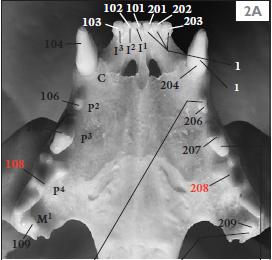

成年猫的牙齿示意图

正常情况下,猫咪应该有30颗牙齿。每颗牙齿都有各自的编号。

但是你看上面这个图,猫咪的一颗叫407的牙齿不见了!!! 而在绿色线圈里应该也还有一颗叫106的牙齿,也毫无踪迹。这是为什么呢? 因为这只猫咪患上了一种叫作牙吸收的疾病。 有研究显示,牙吸收在猫身上的发病率大概在28.5-67%,随着猫咪年龄的增长,出现牙吸收的概率也会增加。当它出现的时候,会发现 牙齿表面出现了粉色的肉芽组织 ,或者 牙龈增生包裹了牙齿 。 类似于像下图猫咪牙齿出现的问题。